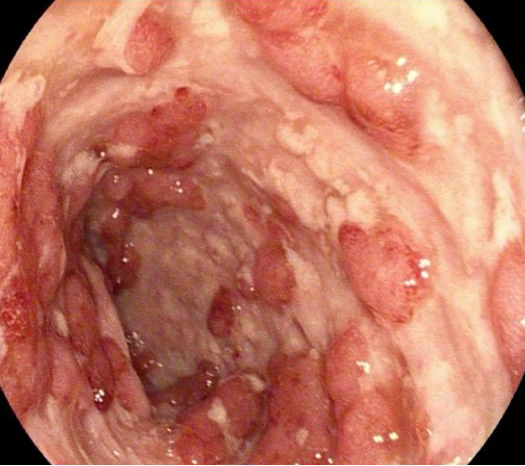

肠腔发现奇形怪状的溃疡会是什么疾病